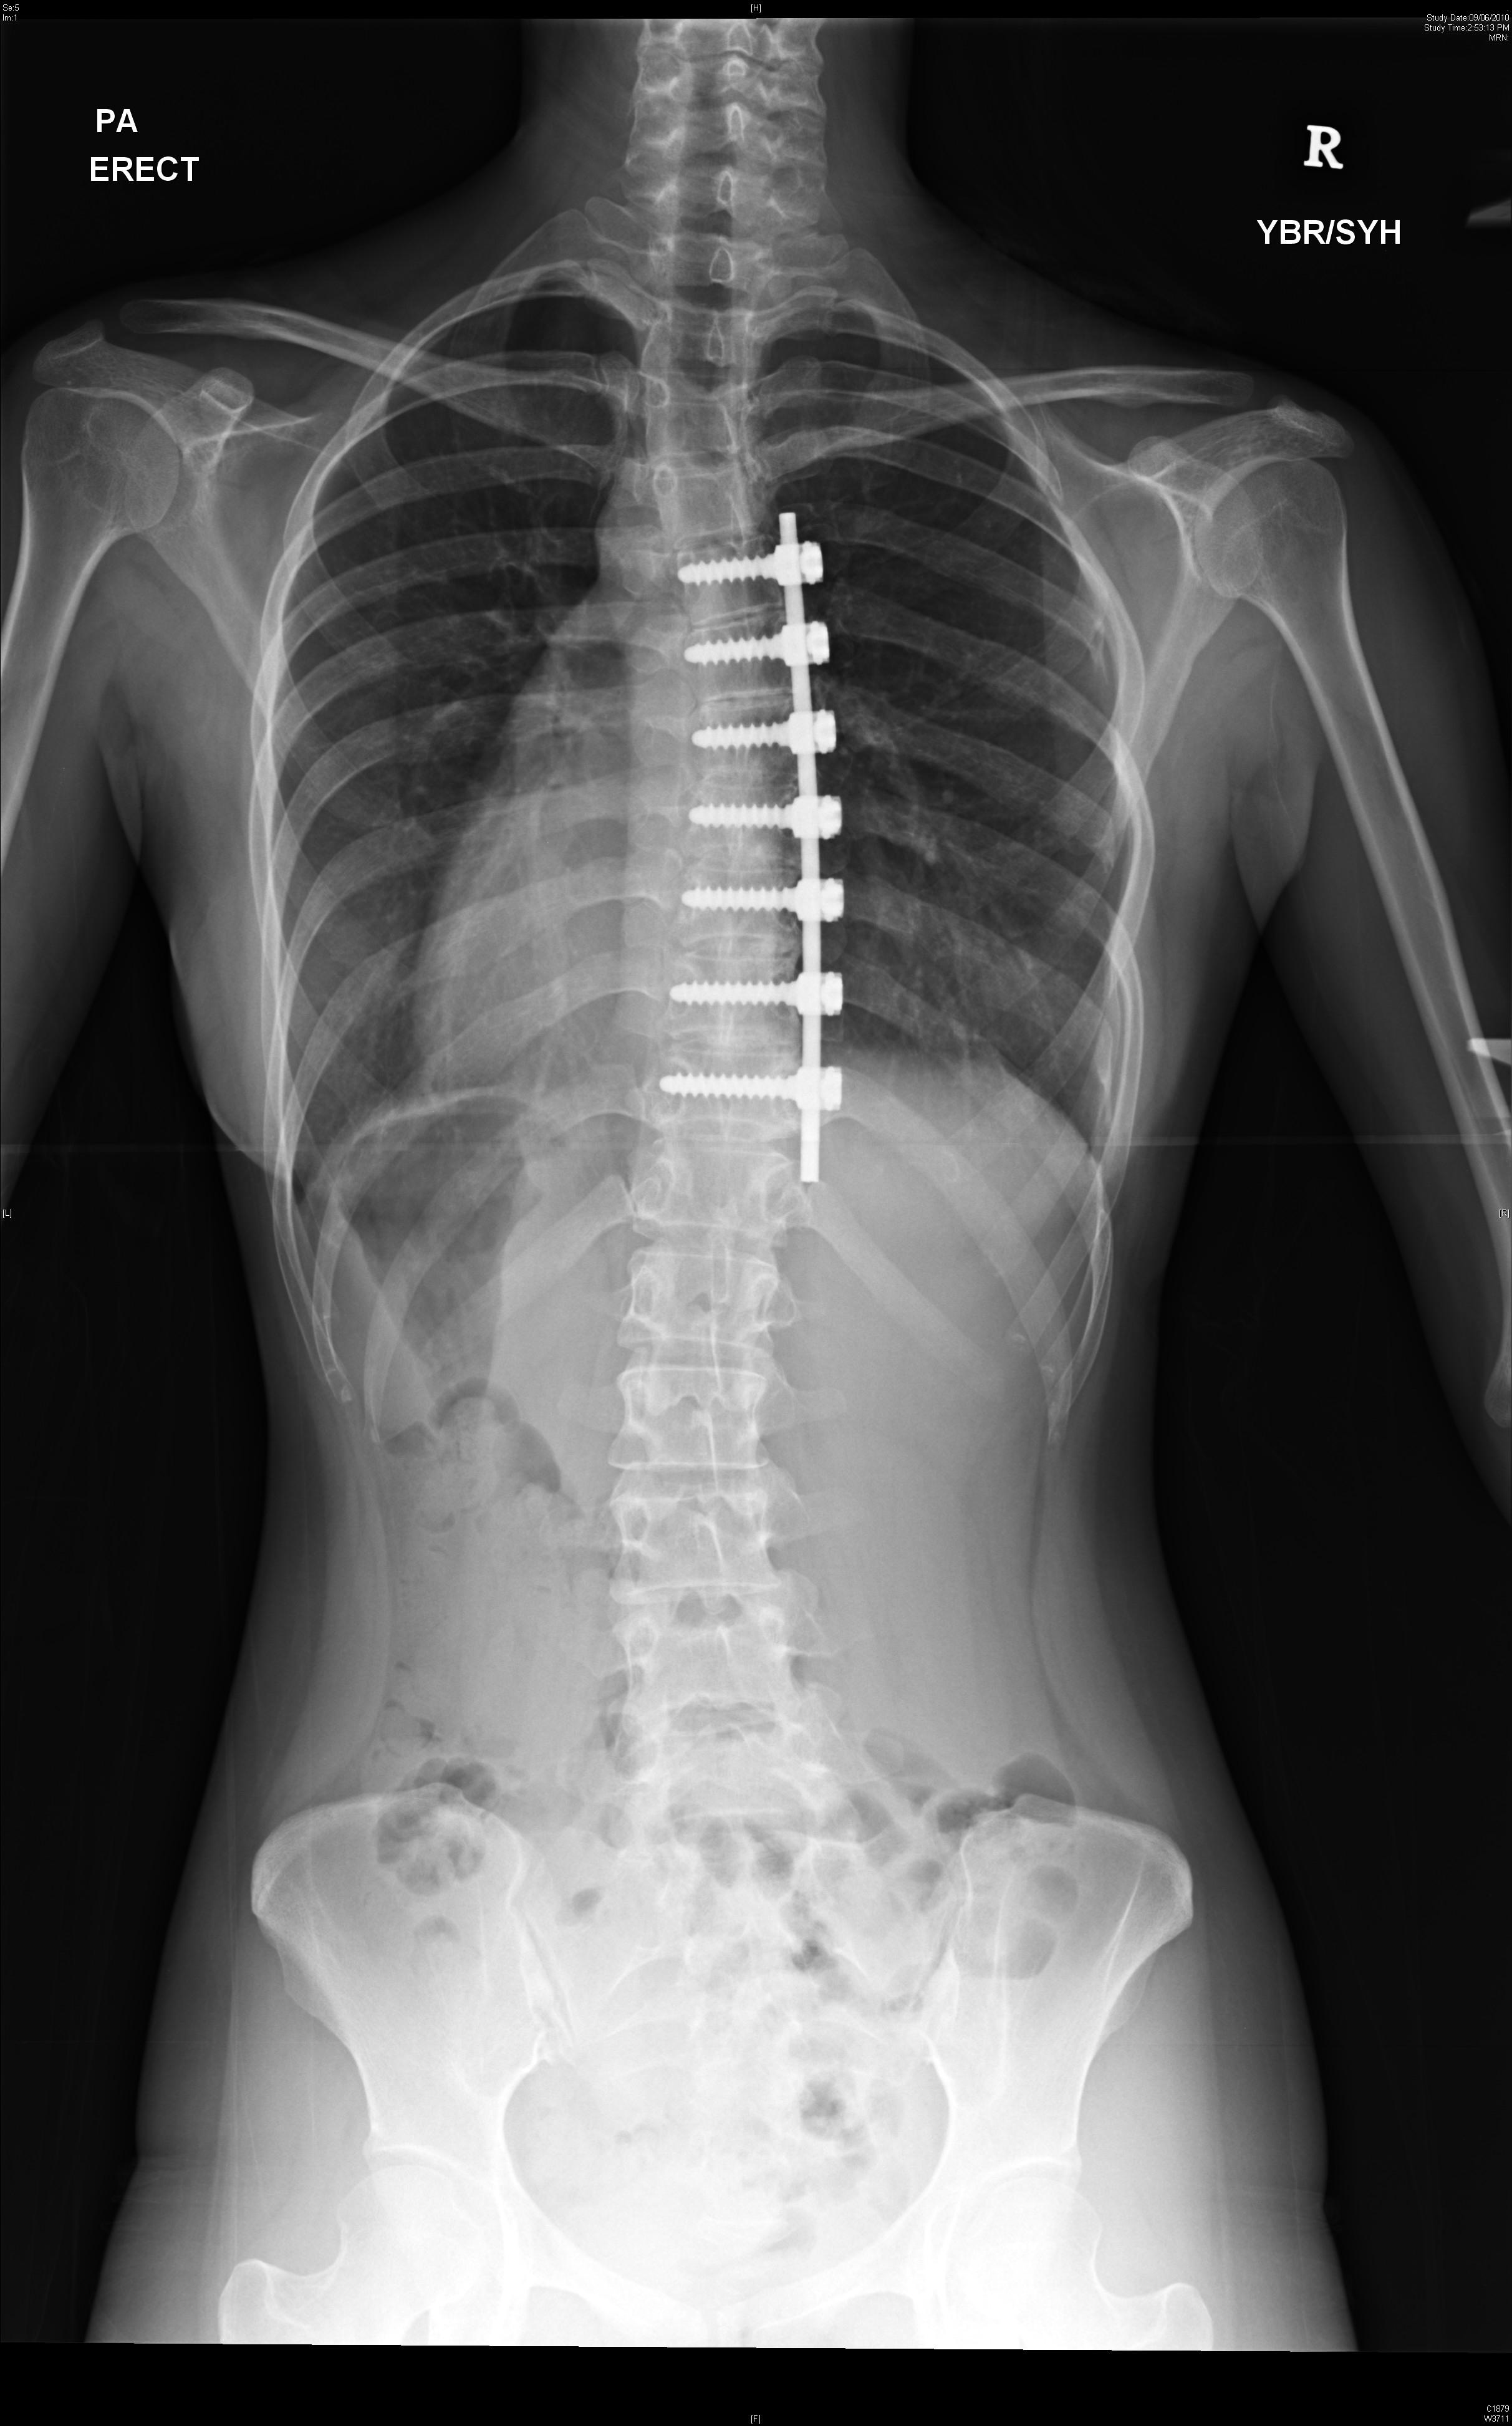

Currently artificial disc replacement can be used for the lumbar or the cervical spine. Many different models have been developed. The majority consists of two metal plates that have teeth to anchor the implant onto the bone of the vertebral bodies. Between the two plates is a metal core or a plastic core made up of polyethylene that allows for motion. Figure 1 shows a lumbar artificial disc replacement. Figure 2 shows a cervical artificial disc replacement.

The technique to insert an artificial disc (whether in the neck or low back) is routine and safe. For the cervical spine it involves going from the front of the neck. For the lumbar spine, it involves going through the abdomen. The procedure begins by removing the gelatinous disc between the vertebrae. Once the disc is removed, two metal plates are pressed into the bony endplates above and below the space now vacated by the disc. Metal spikes hold these plates in place on the bone. Eventually bone will grow over and around the metal plates. In between the metal plates is a metal or plastic core made of a polyethylene. Figure 3 shows the artificial disc placed in the spine.